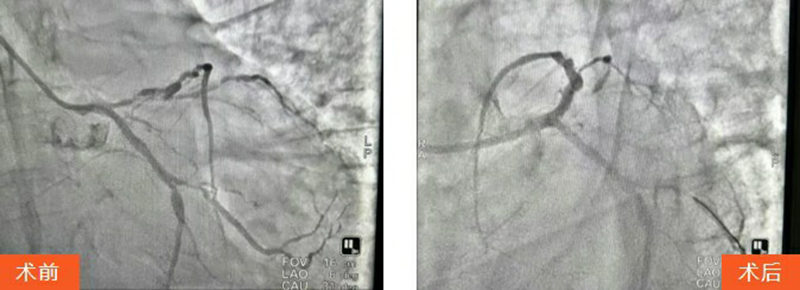

王先生被迅速送往血管介入科行急診PCI(經(jīng)皮冠狀動(dòng)脈介入治療)。術(shù)中,馬建亮主任帶領(lǐng)心血管內(nèi)科專家團(tuán)隊(duì)為其進(jìn)行血管造影檢查,結(jié)果顯示:冠脈三支血管病變,前降支彌漫性病變伴鈣化,次全閉塞累及主干,病情極其兇險(xiǎn)。

手術(shù)過程中患者生命體征不穩(wěn)且煩躁不安,血管介入科團(tuán)隊(duì)全程安撫配合,馬建亮主任團(tuán)隊(duì)果斷采用球囊擴(kuò)張病變血管,成功植入2枚冠脈支架,最終使患者轉(zhuǎn)危為安。

歷經(jīng)緊張救治,手術(shù)圓滿成功。術(shù)后患者恢復(fù)良好,生命體征平穩(wěn),現(xiàn)已轉(zhuǎn)入心血管內(nèi)科病房繼續(xù)觀察?;謴?fù)意識(shí)的王先生感慨:"要不是治療及時(shí),我這條命可真保不住了。"